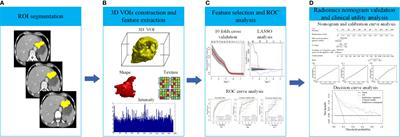

ORIGINAL RESEARCH

Published on 02 Sep 2021